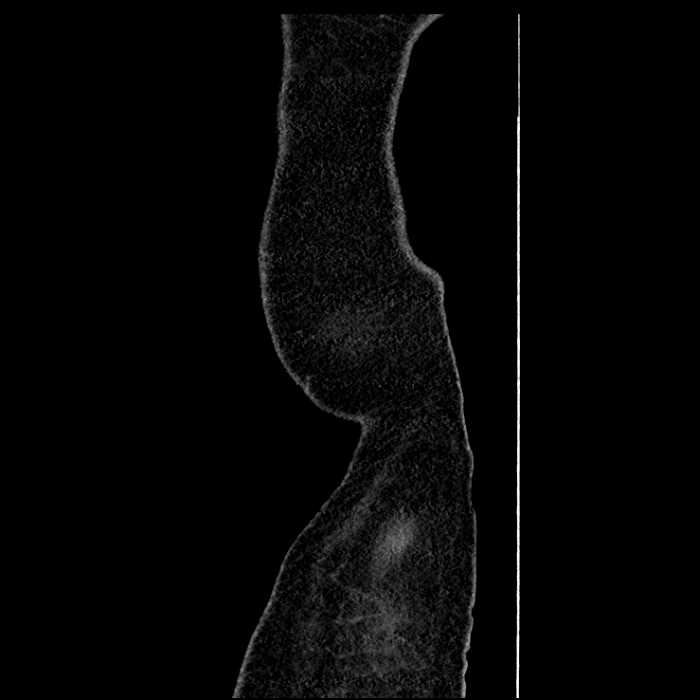

• The classic CT imaging appearance is a double target sign with internal low density surrounded by an internal enhancing rim (capsule) and a low density external rim (edema)

Hepatic abscess showing the double target sign with low density internally surrounded by a thin inner enhancing rim (red arrow) and ill-defined outer low density rim (yellow arrow). Blue arrow indicates an internal septation. Red arrows: additional smaller subcapsular abscesses. Red arrow: focal contained perforation associated with diverticulitis.